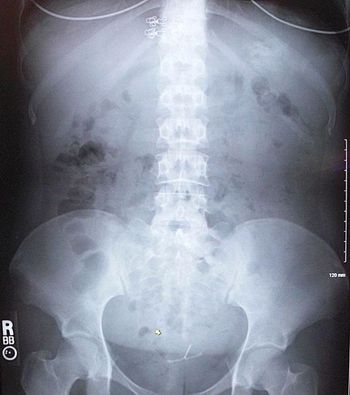

The 21-year-old recently immigrated from Mexico. She has had trouble swallowing both solids and liquids x4 months. The clue to diagnosis is a subtle one.